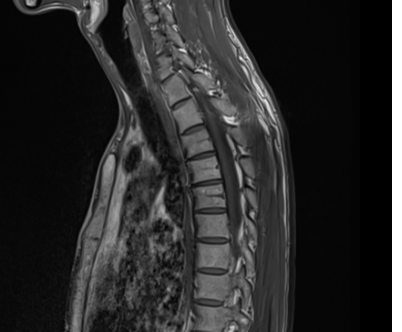

척추 mri를 찍어서 봤는데 저런식으로 홈이나 금간것저럼 보이는게 있는데 저건 뭔가요???

뼈에 금이 간게 아니라면 뭔지 궁금합니다

이런 경우에 골절이 아닌지 오해하시는 경우가 많은데 골절이 아닙니다.

골절의 경우에는 T1 영상에서 조영이 떨어지고 fat suppression T2 영상에서 조영이 증가하는 소견을 확인해야합니다.

골절이 아니면 왜 저렇게 보이는지 까지는 제가 잘 모르지만 저 소견을 이상소견으로 보이는 않습니다.